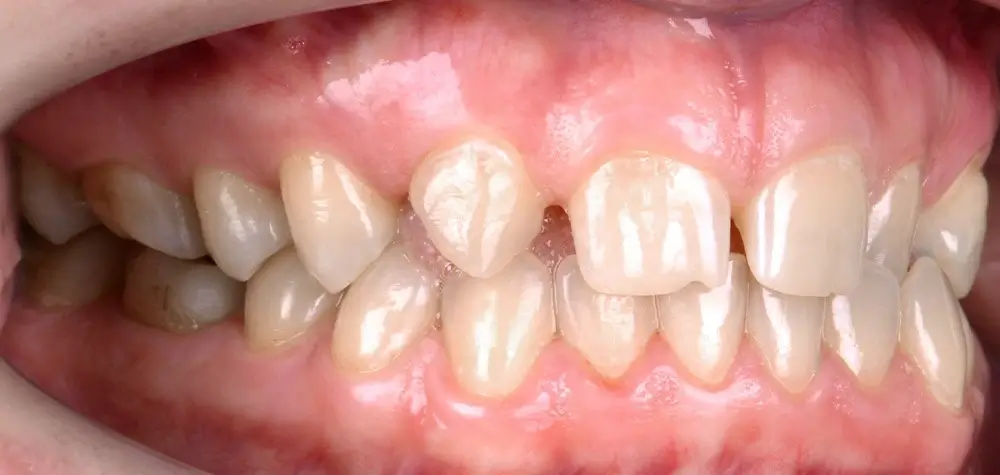

Кейс 8

Бажанова Ольга Валерьевна

Количество кап ВЧ 24

Количество кап НЧ 24

ДО